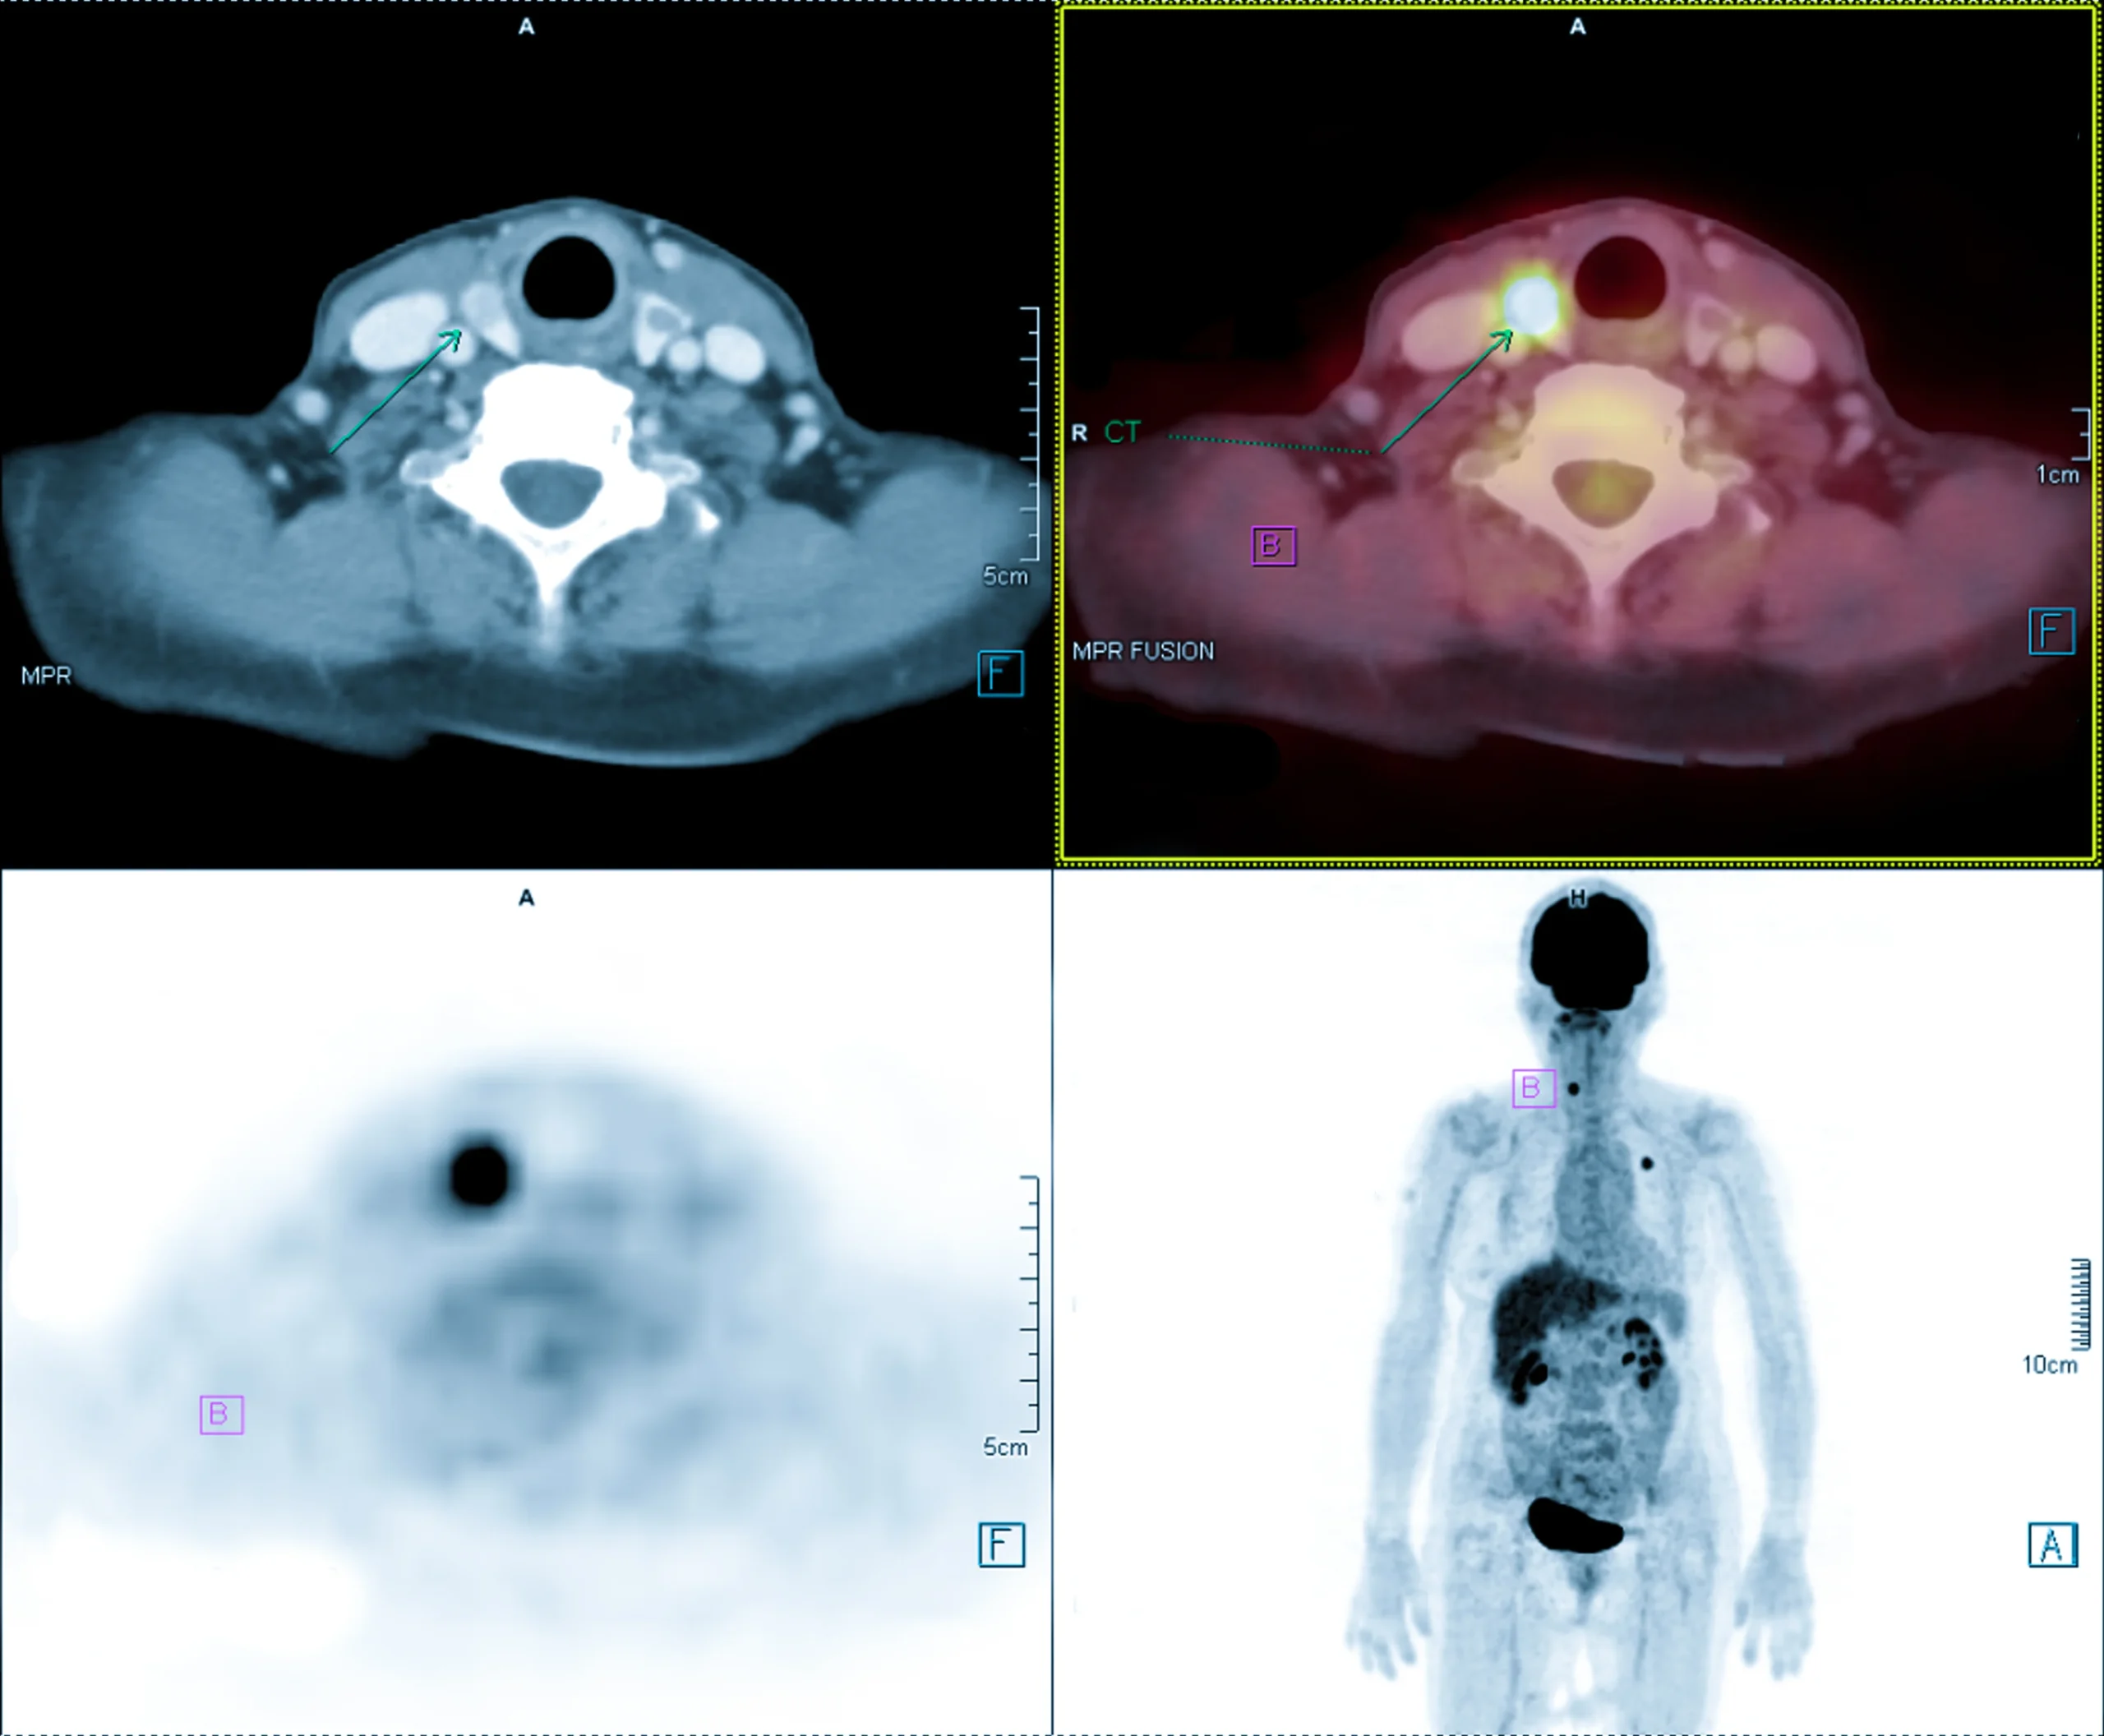

İnsan vücudundaki doku ve organların fonksiyonlarını incelemek ve değerlendirmek için kullanılan bir görüntüleme testidir. PET/BT taramasında ise PET taraması, BT taraması ile birleştirilerek vücudun 3 boyutlu görüntüleri elde edilir. PET/BT taraması, vücuttaki anormal durumları tespit etmek için az miktarda radyoaktif madde hastaya enjekte edildikten sonra yapılır. PET/BT taraması sonrasında hastanın görüntüleri detaylı şekilde inceleme yapılarak organ, doku ve hücresel düzeydeki değişiklikler tespit edilebilir.